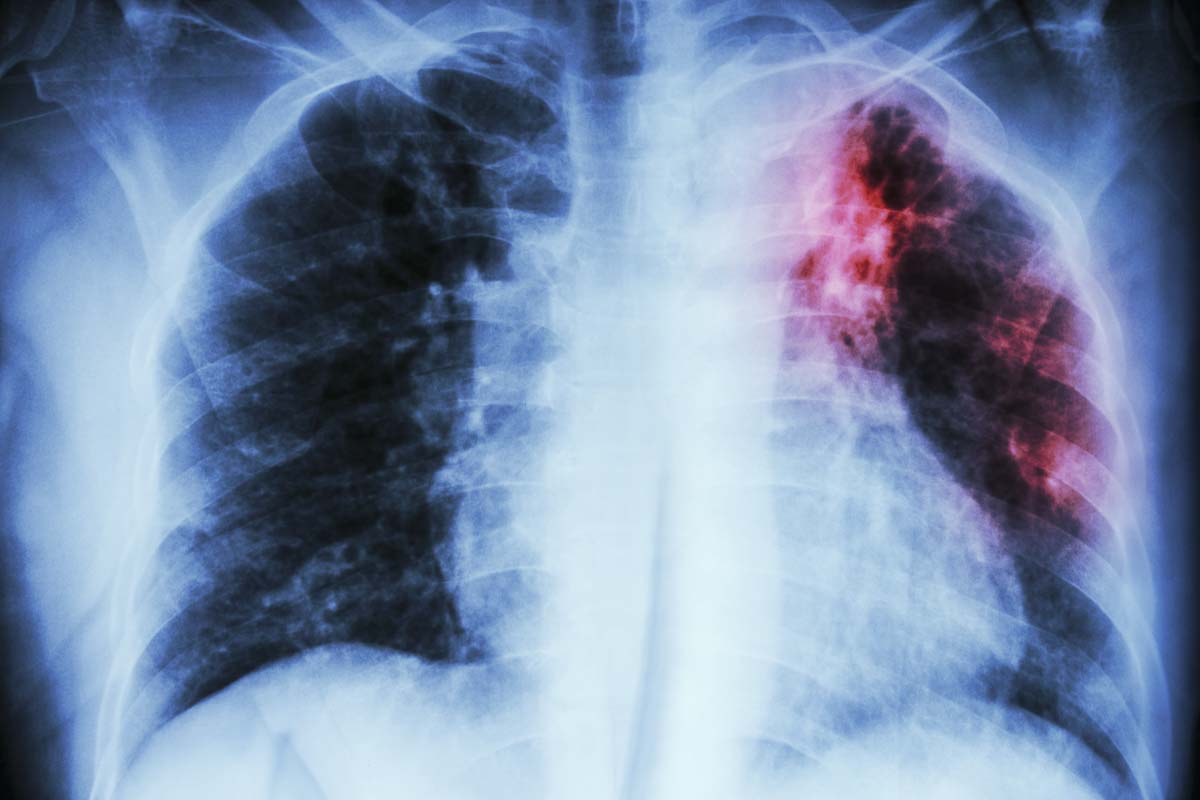

Tuberculosis is caused by a germ that is spread from person to person through the air. TB is usually spread through prolonged close contact with someone who is contagious. Active TB disease does not develop immediately after a person is infected. Early identification and treatment of people who are infected can prevent them from developing active TB disease.